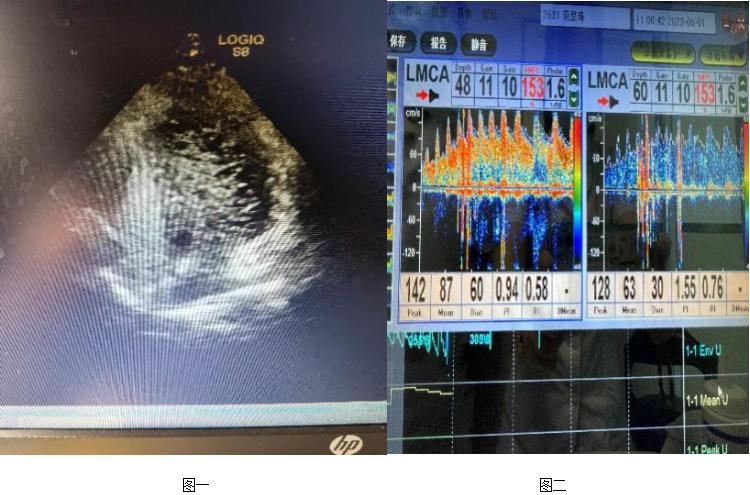

广东三九脑科医院神经内二科主任钟水生接诊后,为患者完善专科查体,结果都正常。入院后完善右心声学造影:静息状态下3-6个周期内,房水平右向左分流3级,Valsalva动作释放时,房水平3-6个周期内左房、左室可见持续性浓密造影剂气泡回声,静息状态及Valsalva动作房水平右向左分流均3级,考虑存在卵圆孔未闭可能性大(图一)。TCD发泡试验阳性,支持右向左分流(图二)。心脏彩超:心脏未见异常。进一步完善头颅MR平扫+半球动脉(MRA) 示部分空蝶鞍,右侧大脑前动脉A1段发育不良(图三)。